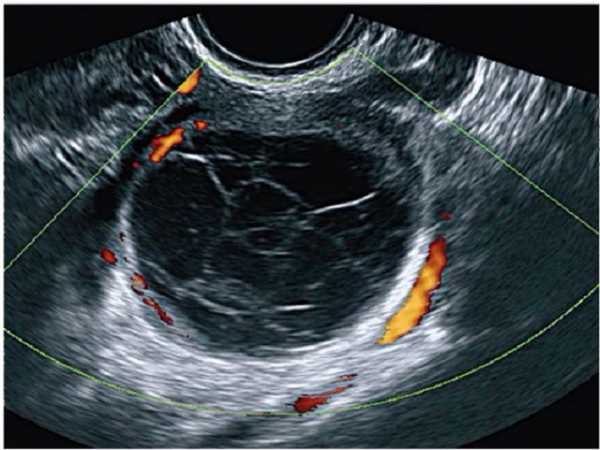

На этом узи снимке вы видете доминирующий фолликул преовуляторного диаметра, а именно от 19мм. Тесты на овуляцию показывают 2 полоски. Вторая полоска классически ярчает и пациентка уверена, что овуляция есть. Если мы посмотрим эту пациентку через 7-10 дней, скажем в промежуток от 21 до 25 дня, мы увидим такую картину:

А вот к 5-6 дню от предполагаемой овуляции картинка начинает меняться, фолликул изменяет контур и приобретает гиперэхогенные перемычки, характерные для желтого тела.

И через неделю, дней десять мы видим желтое тело.

Диагноз - лютеинизация неовулирующего фолликула

О полноценности желтого тела также нужно судить по характеристикам кровотока в артериях этого самого тела.

В сосудах нормального желтого тела снижение ИР в среднем до 0,44 отмечается уже на 2-й день после овуляции, причем этот показатель практически не меняется в течение первых 5 дней лютеиновой фазы. В лютеиновую фазу ИР ступенчато повышался в среднем до 0,47 и в дальнейшем постепенно увеличивался в среднем до 0,53 к концу лютеиновой фазы. А вот ИР выше 0,53 говорит о неполноценности лютеиновой фазы.